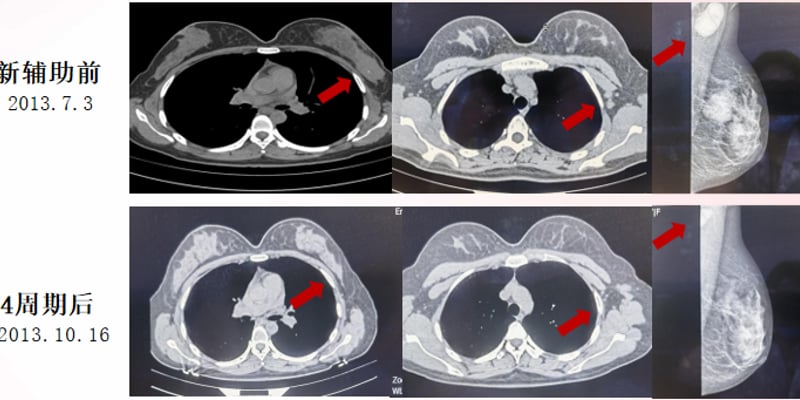

图1